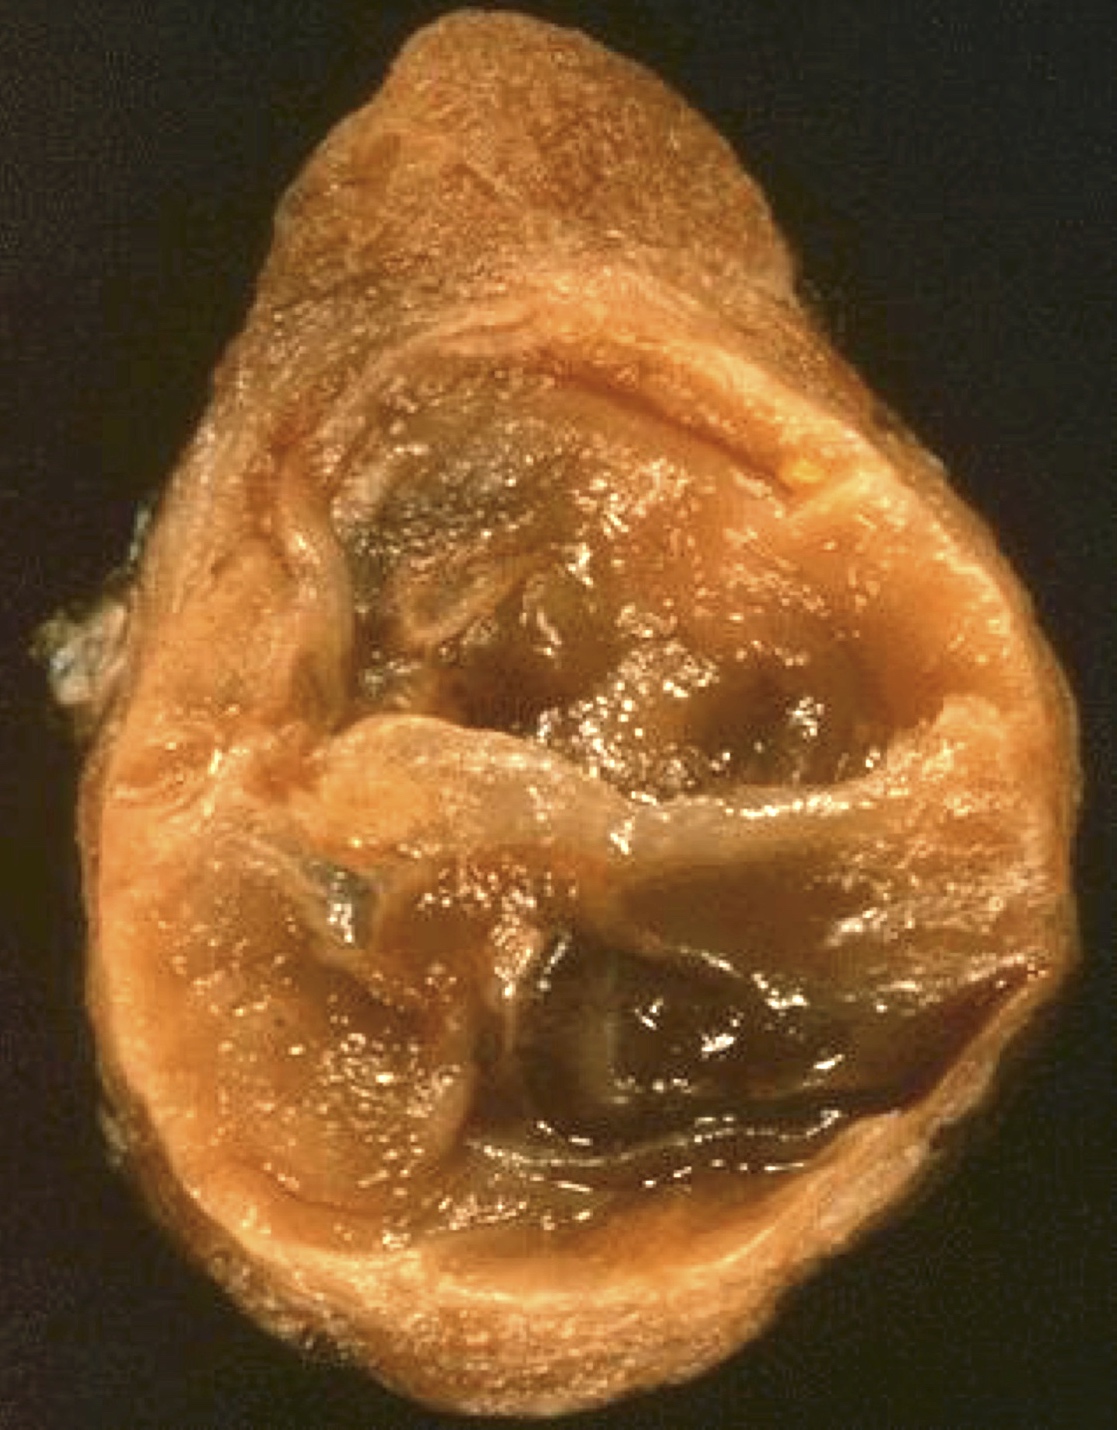

Gross description

- Solitary, encapsulated nodule; multiple if familial

- Variable size (1 - 10 cm)

- Solid, gray-white, tan to light brown

- Secondary changes: hemorrhage, cystic change, fibrosis, calcification, infarction; may develop post-fine needle aspiration cytology

- Rarely black; especially seen with minocycline therapy

Gross images

Contributed by Andrey Bychkov, M.D., Ph.D., Mark R. Wick, M.D. and AFIP

Images hosted on other servers: